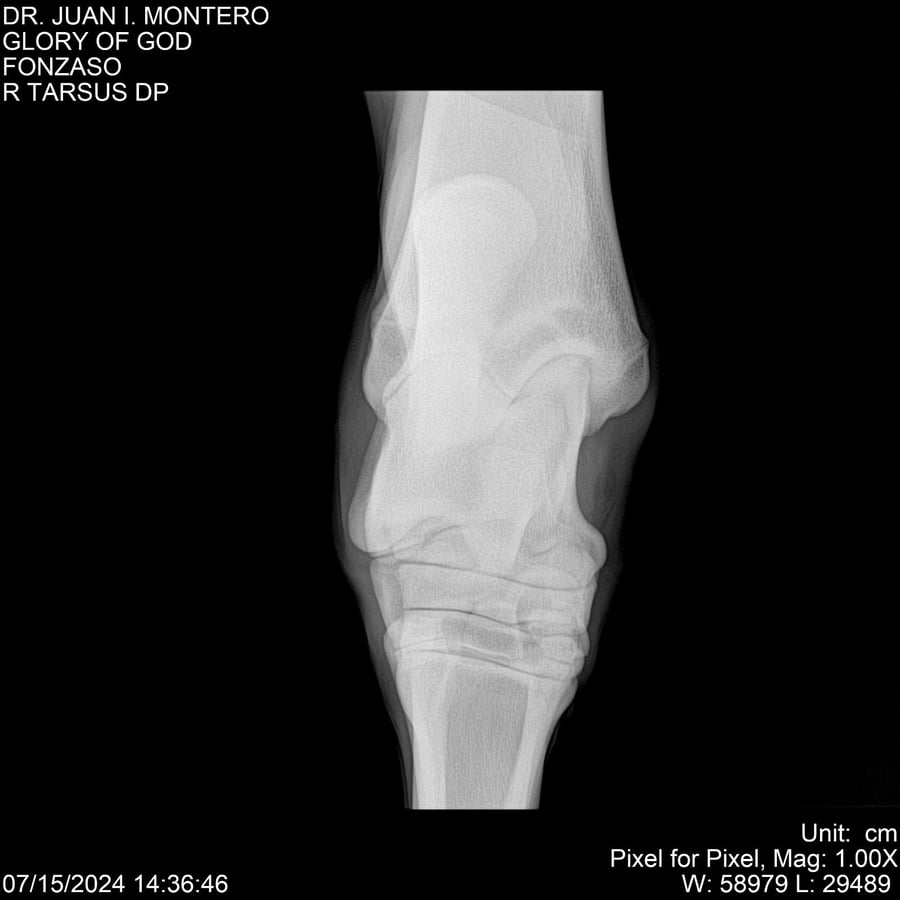

LOTE 10, GLORY OF GOD 🔥 🔥 🔥 Lote Anterior Volver al remate Lote Siguiente Ficha Contacto Montevideo - Ficha del Lote Identificador: #281389 Categoría: Yeguarizos Montevideo - 115 Visualizaciones ClicData Contacto Empresa: Abelenda N. R., Walter Hugo Nombre*: Teléfono* : E-mail* : Mensaje Enviar Registrese gratis Este contenido Exclusivo está disponible sólo para usuarios registrados Ingresar